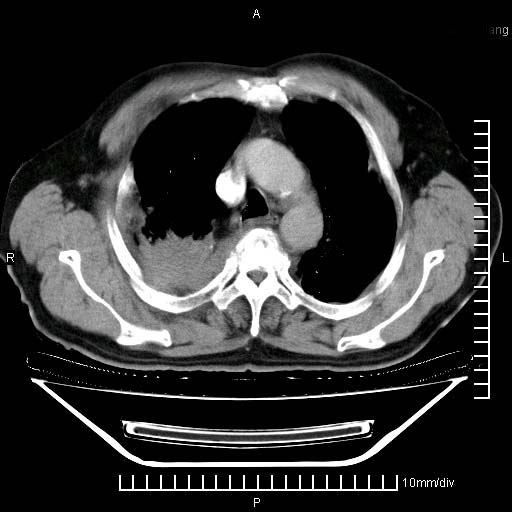

标题: CT24043:胸部增强:男性,60岁

既往肺结核,近10几天,咳嗽,咳痰,右侧胸痛,疼痛较明显,右上肺斑块考虑结核灶胸膜粘连,增强,可惜动脉期没有定好,未见强化,可延迟4分后又见较明显强化,中心见低密度影,如果说结核是边缘强化,可这个灶强化的面积挺大的,让人很挠头。

肺结核、胸膜增厚。

1)两肺继发性肺结核。2)右侧胸膜增厚+少量胸腔积液。